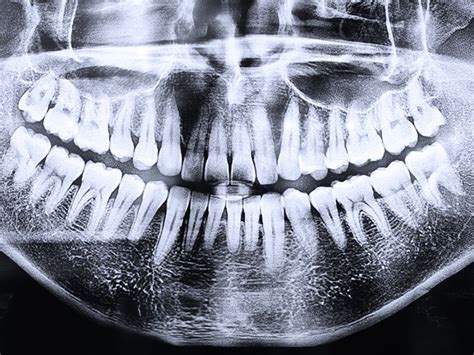

Las radiografías panorámicas (término técnico: ortopantomografía) se utilizan para obtener una visión general de toda la cavidad bucal con el fin de detectar anomalías como inflamaciones radiculares, tumores y abscesos o ver la posición de las muelas del juicio que aún no han erupcionado. A diferencia de las radiografías intraorales, la película o el sensor se encuentra fuera de la zona bucal.

Radiografía panorámica dental.